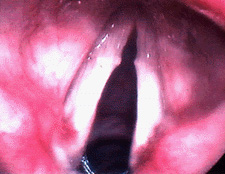

Close up of a vocal cyst

The image to the right shows a vocal fold cysts in a soprano who had significant hoarseness. This picture was taken with a stroboscopic light source through a flexible fiberoptic scope. The vocal folds are therefore "frozen" in time at the point of closure. Note that the folds cannot close completely due to the cyst. This cyst was removed surgically and the voice returned to normal.

Close up of a large right vocal cyst

This image shows a close up view of a larger cyst in a different individual. This photograph was taken at the time of surgery for removal of the cyst. Notice that the left vocal fold is slightly thickened immediately opposite the cyst. This thickening has developed in response to the cyst, and should resolve spontaneously after removal of the cyst.‌